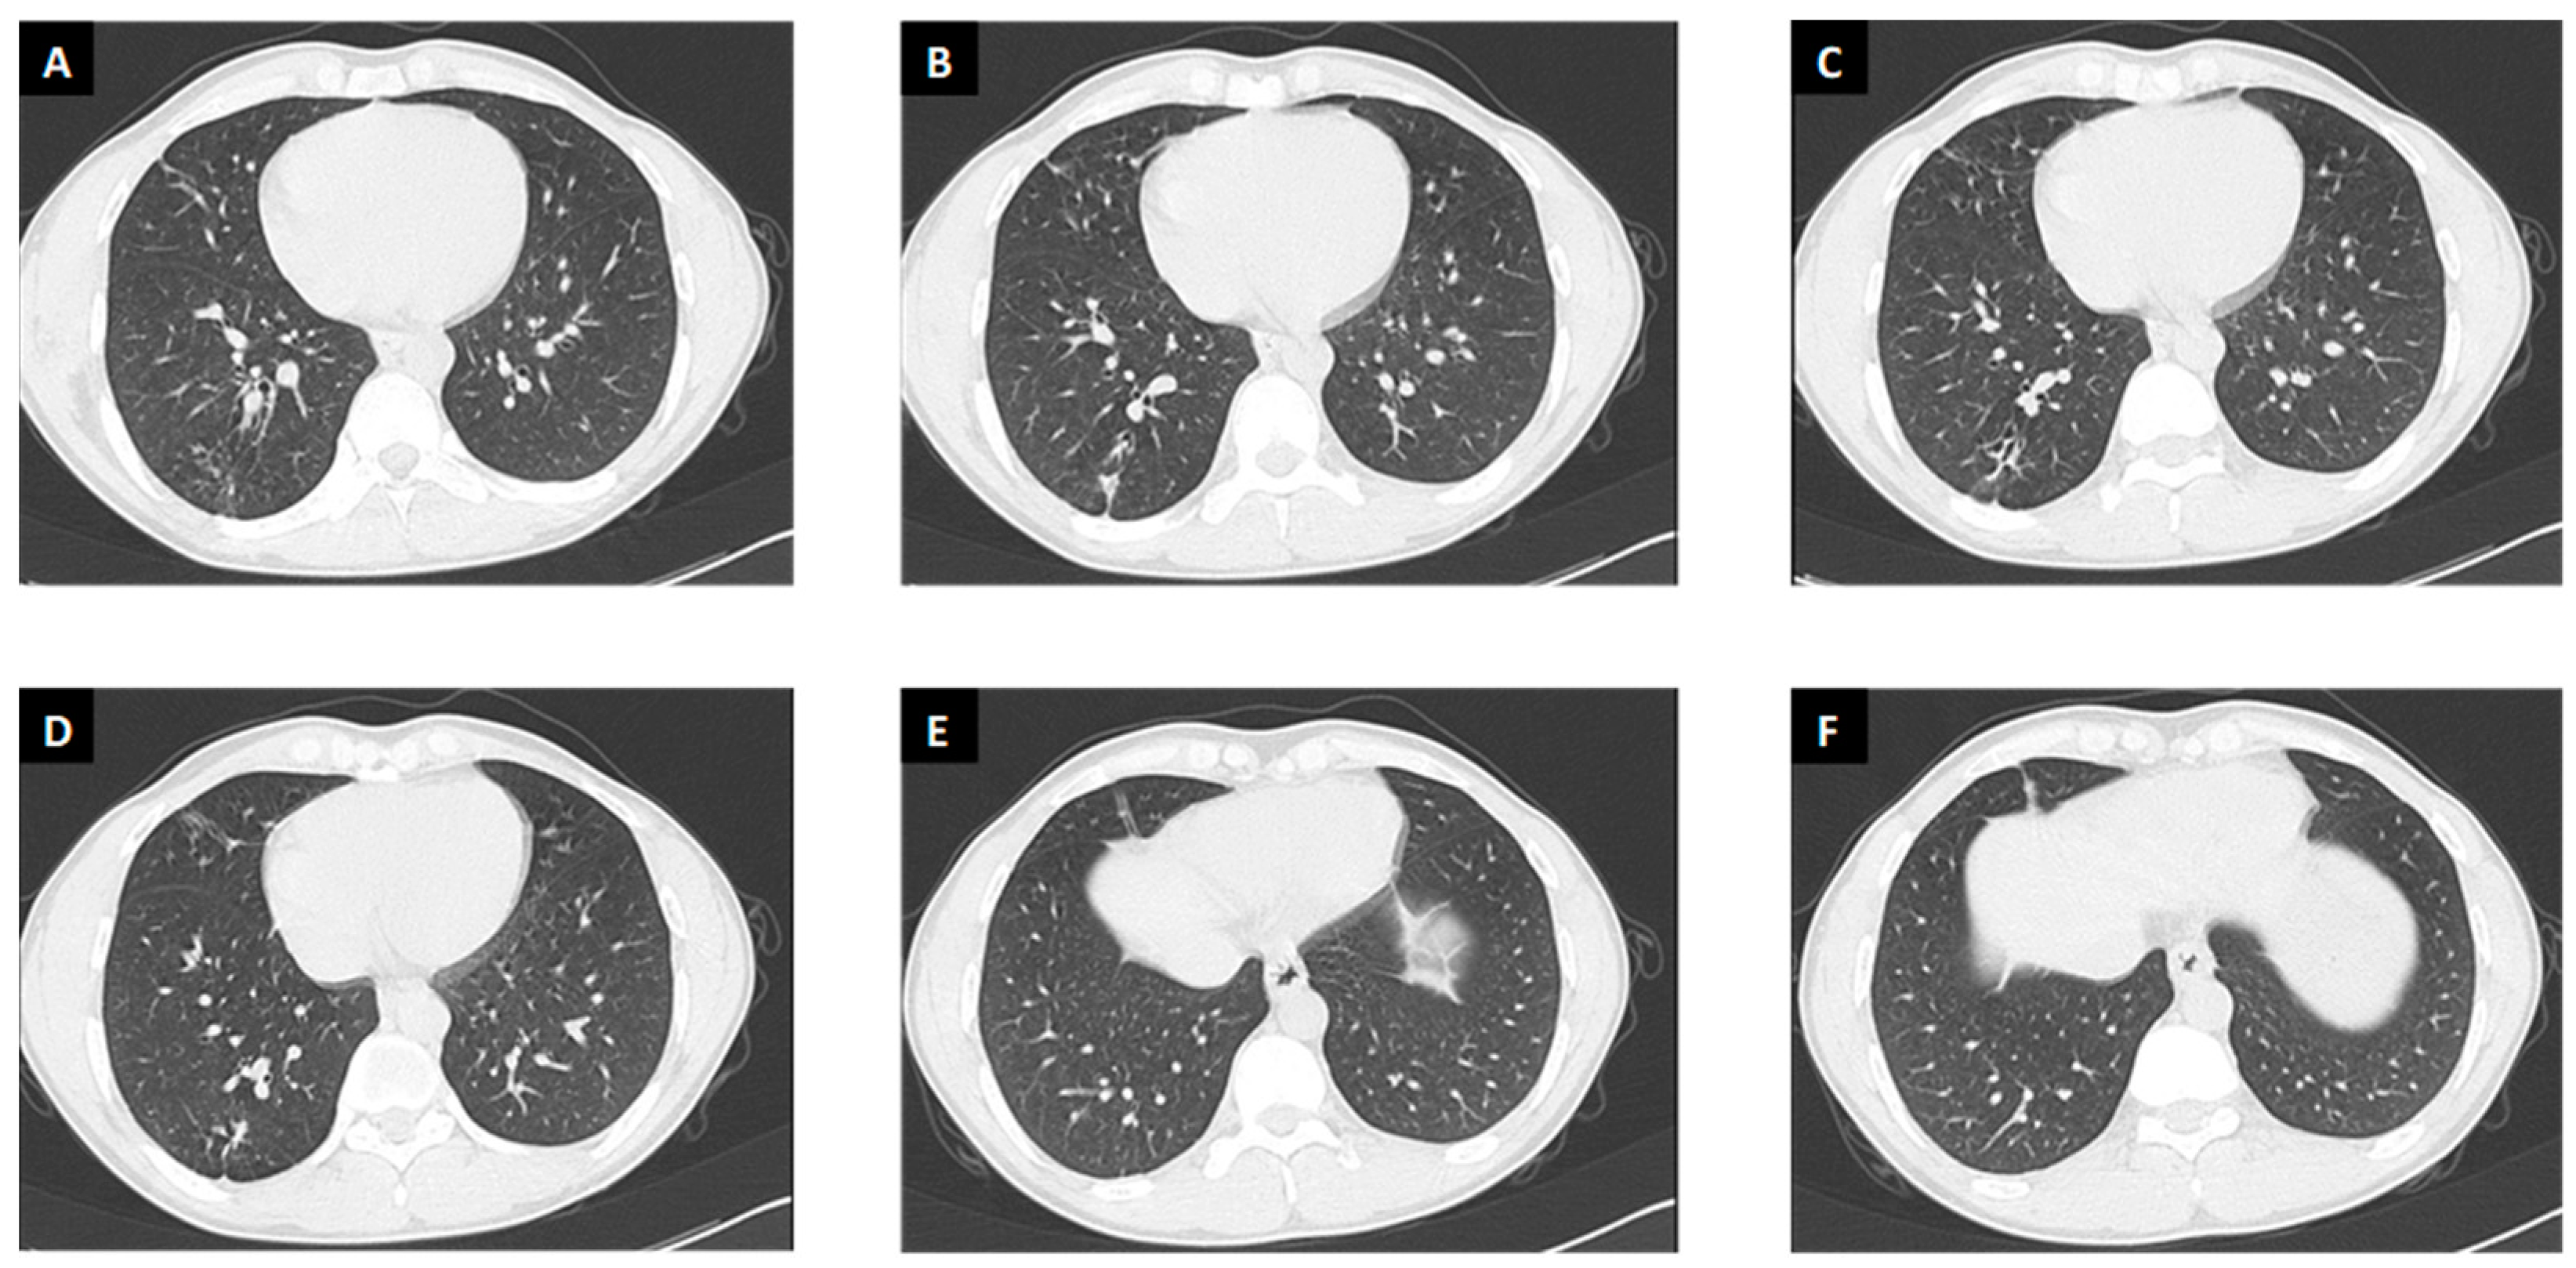

3.2.3. Radiological Findings